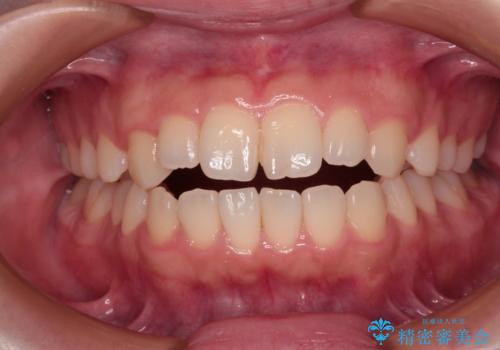

【審美装置】前歯で噛めない!抜歯しないで治したい

MARPEで非抜歯矯正|オープンバイトと八重歯を改善